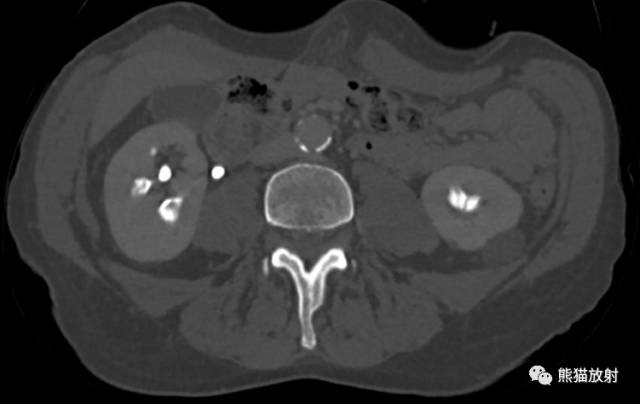

CT urogram (2017): Noncontrast images demonstrate multiple bilateral nonobstructing renal calculi, the largest measuring 6 mm in the right kidney. Some of the calcifications could represent nephrocalcinosis — for example, those in the upper pole of the right kidney. The kidneys show symmetric enhancement without suspicious renal mass. Multiple bilateral exophytic simple renal cysts are noted, the largest in the midpole of the right kidney measuring 3.6 x 4.3 cm. There are additional subcentimeter low-attenuation lesions that are too small to characterize. There is a “paintbrush sign” appearance to the renal medullae in keeping with a history of medullary sponge kidney. There is mild bladder wall thickening and trabeculation that may be related to chronic outlet obstruction. Further evaluation is deferred to cystoscopy.

CTU:CT平扫可见双肾多发非梗阻性肾结石,右肾最大者直径约6mm,其中一些钙化可能代表肾结石,例如,右肾上极的那些。肾脏对称性强化,未见可疑肾肿物。双肾可见多发单纯性肾囊肿,大者位于右肾中部,大小约3.6 x 4.3 cm;另可见不足1cm的低密度灶,其太小而不能显示。肾髓质表现为“毛刷征”,符合髓质海绵肾。膀胱壁轻度增厚并小梁形成,与慢性流出道梗阻有关。进一步评估需膀胱镜检查。